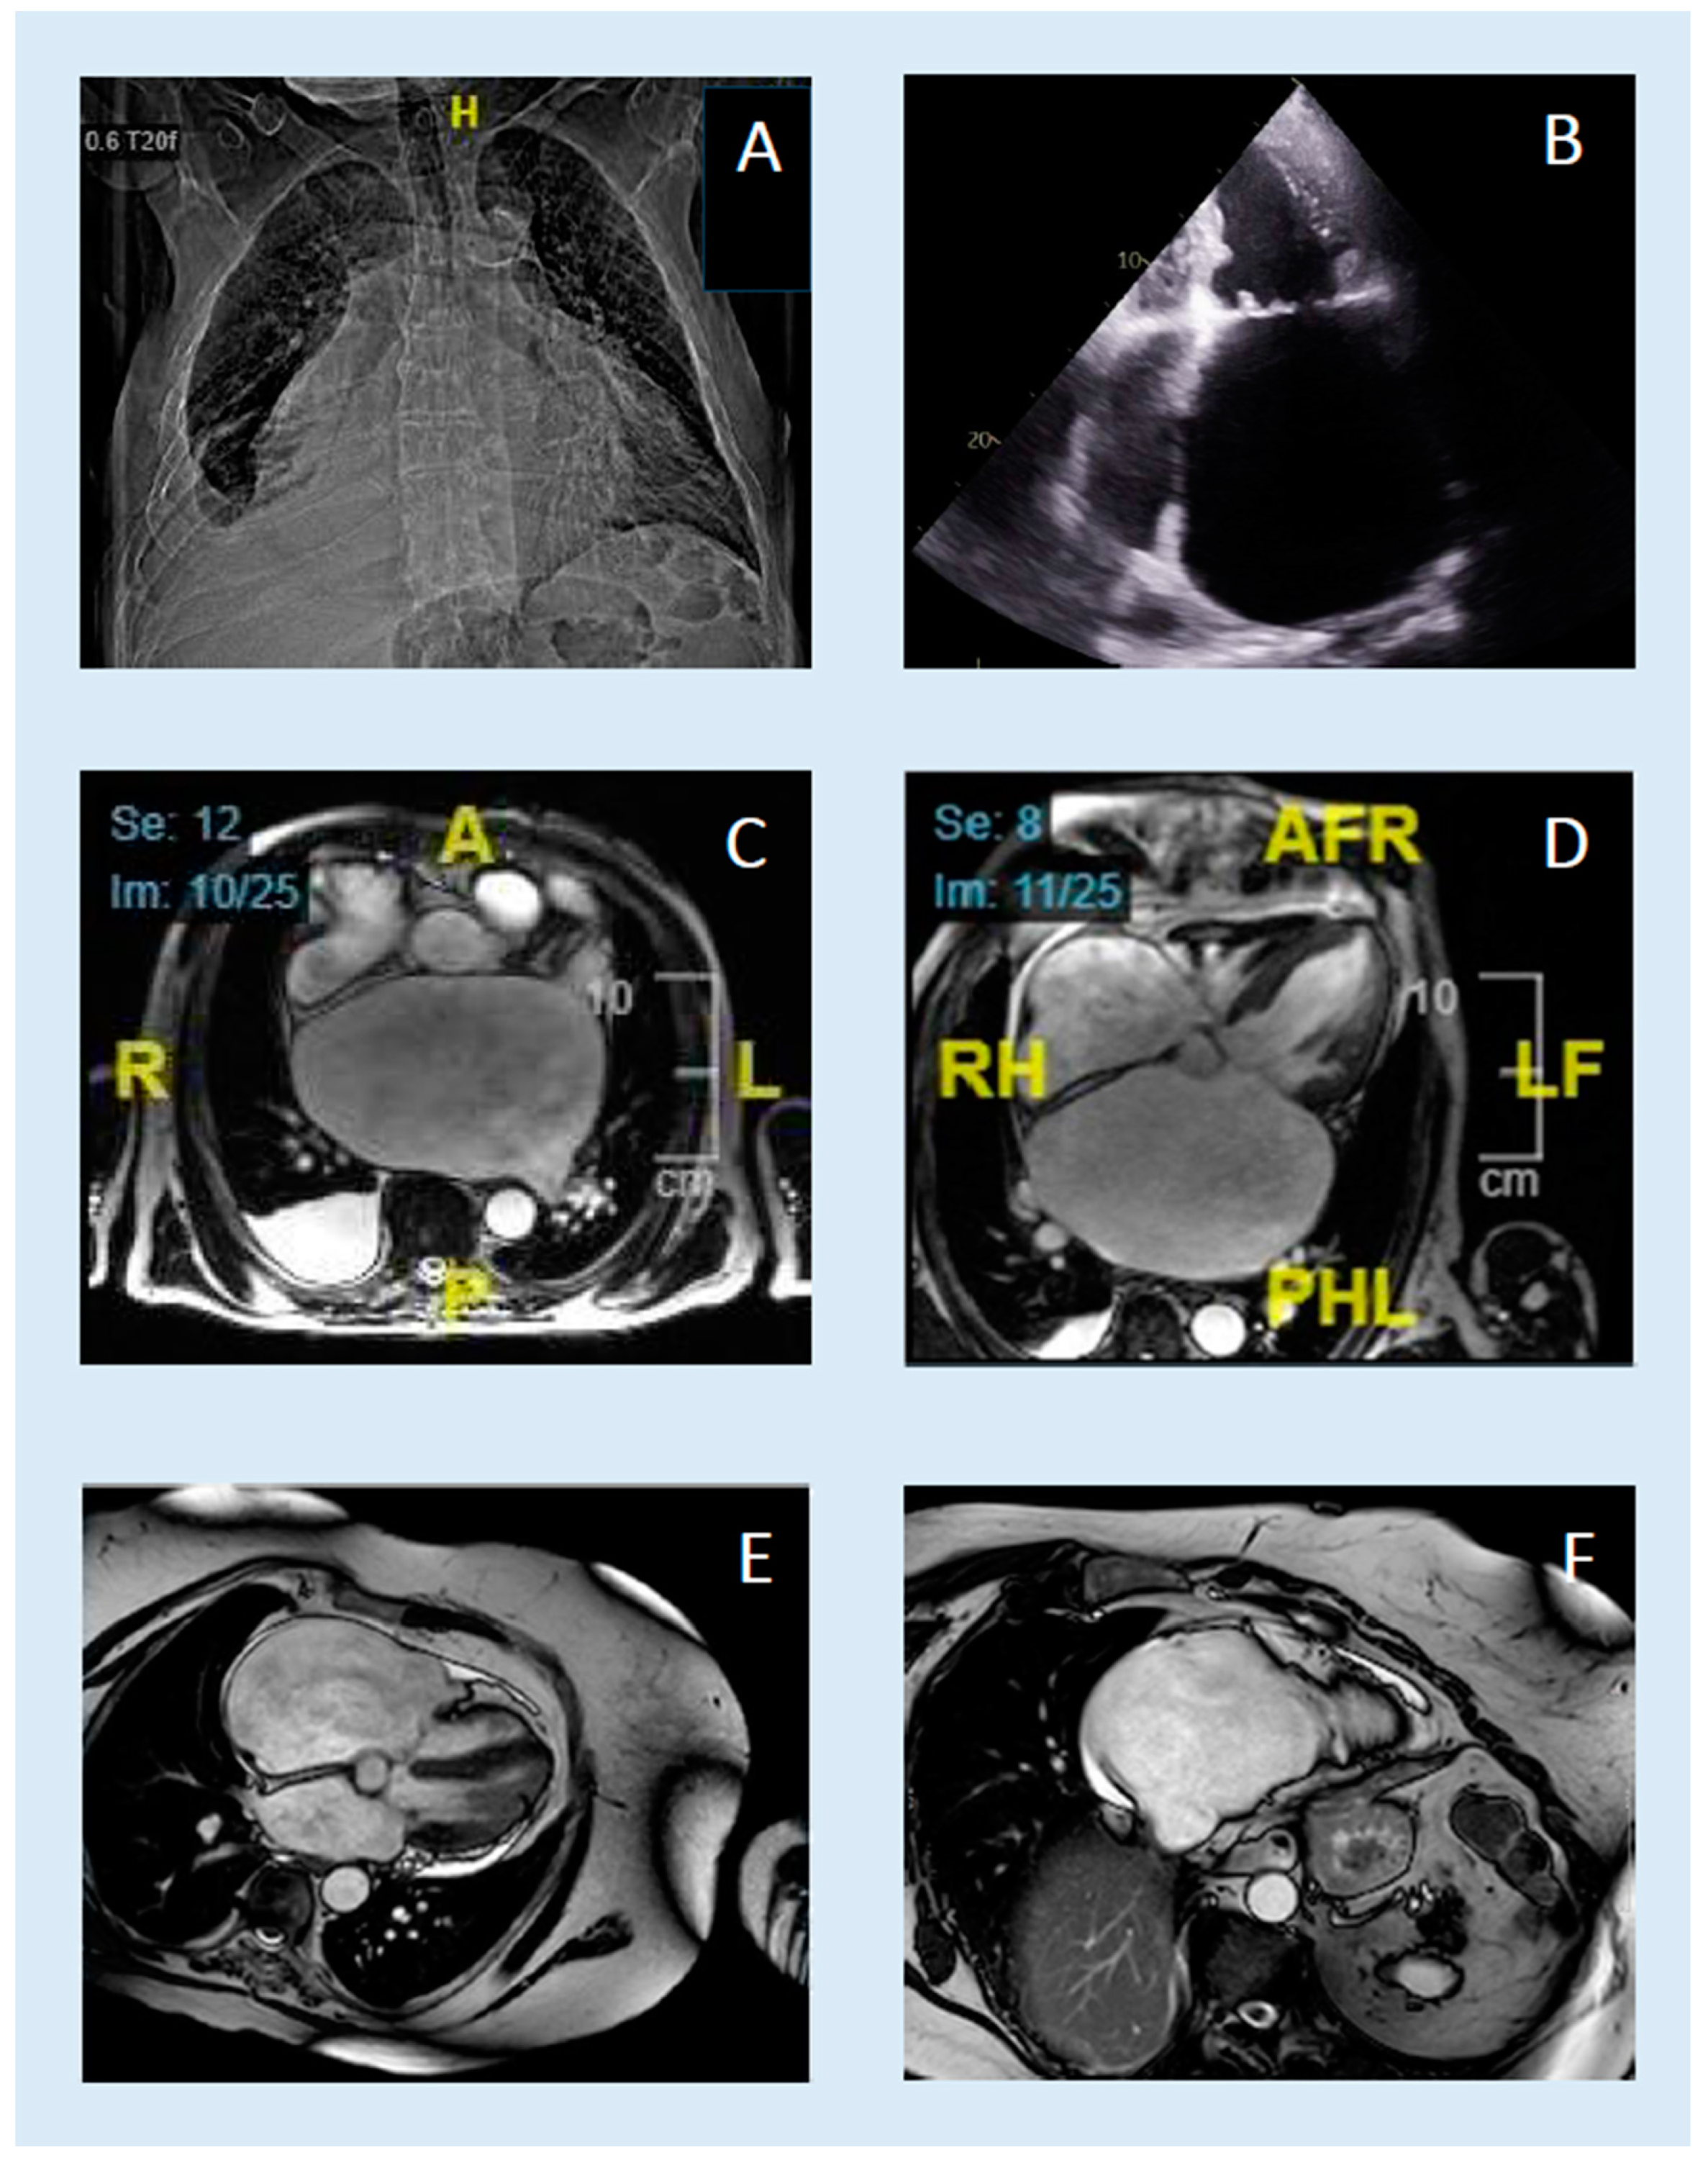

| A | 89 (Anomaly suspected by chest X-ray since adolescence) | male | 2.0 | dyspnoea, dizziness, syncope | Cardial decompensation with reduced LV function | no reduced LV function, giant left atrium, moderate mitral regurgitation | permanent atrial fibrillation | recompensation with diuretics | No symptoms (5) | none | 2D-Echo + CMR |

| A | CMR | 63 | 184 | 1472 | 747 | 131 × 134 | 132 × 145 | 151 | 138 | Diagnosis confirmed |